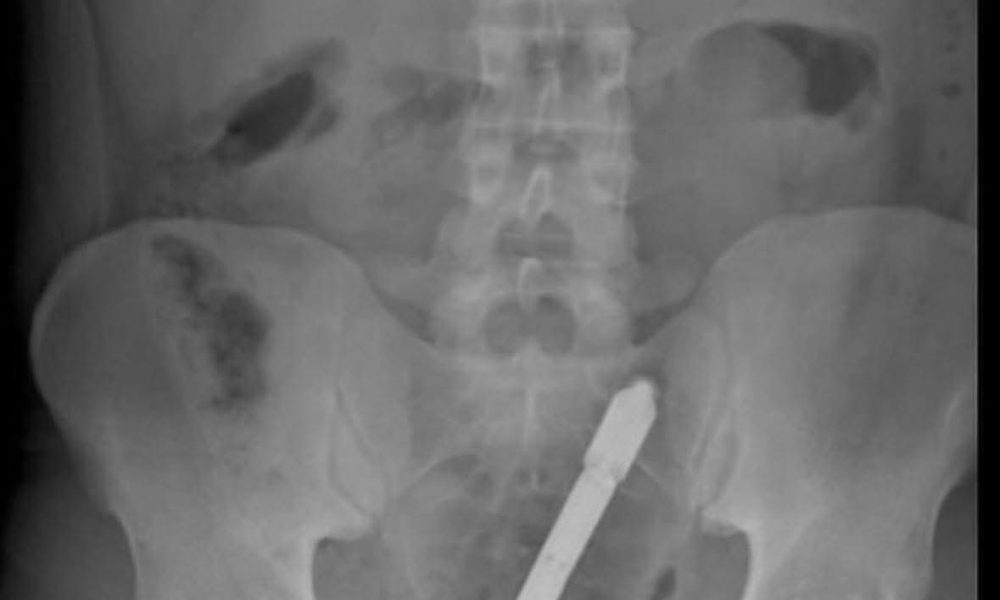

Llevan hombre a hospital de Mao con palo incrustado en parte trasera. junio 24, 2025 VALVERDE.- Una emergencia inusual se presentó la noche del lunes, en...